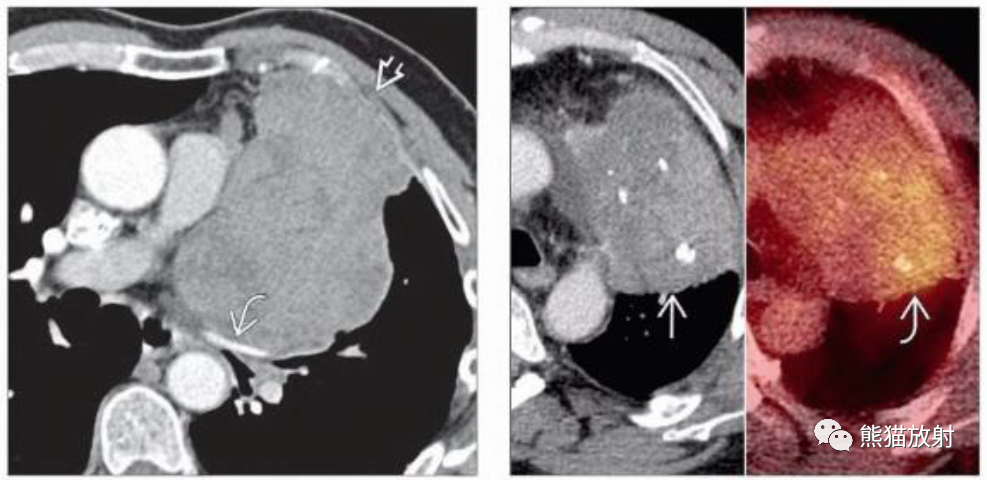

(左) 轴位ct显示左前纵隔胸腺瘤,边缘不规则,邻近纵隔脂肪浸润。手术中证实纵隔脂肪浸润 (IIa期) 。

(左) 胸腺癌。CT显示一个巨大不均质强化的左前纵隔肿块,侵犯左前胸壁,对纵隔血管产生占位效应。胸膜转移可见于胸腺恶性肿瘤,但它是侵袭性胸腺瘤的特征。

(右) 胸腺类癌。轴位CECT和PET/CT图像显示左前纵隔肿块伴钙化、明显不均质强化,PET/CT的FDG代谢增高。